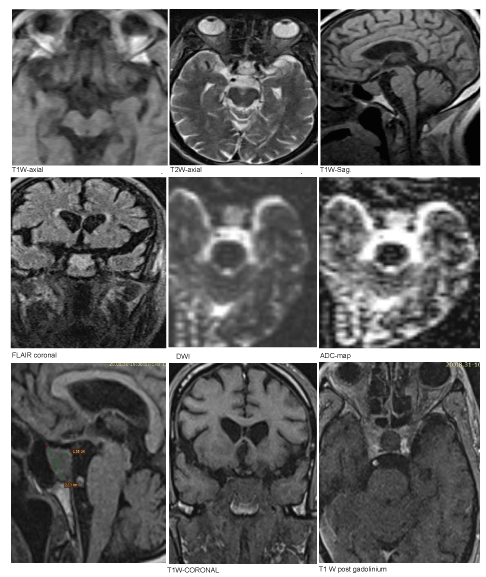

He was admitted to the general medical ward for further workup; with a working diagnosis of quadriparesis, hyponatremia, and acute urinary retention. Later the Magnetic Resonance Imaging (MRI) revealed a Pituitary macro-adenoma (Figure 1). The findings from Electromyogram (EMG) Test & Nerve Conduction Study (NCS) were suggestive of mild to moderate sensory-motor polyneuropathy.

Figure 1: MRI of the brain.